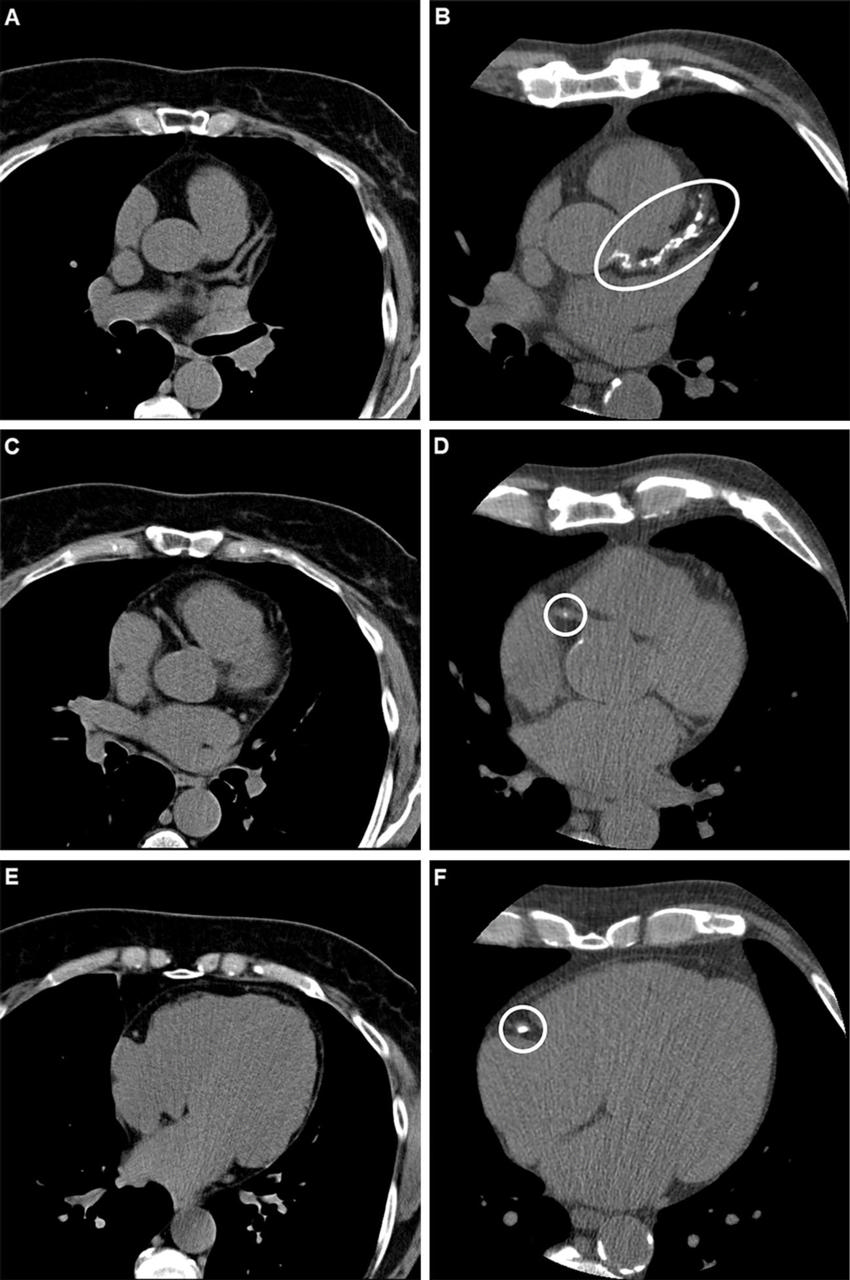

Figure 2. Example axial noncontrast CT scans in (A, C, E) a participant with a coronary artery calcium (CAC) score of 0, no signs of coronary artery disease at CT, and no major adverse cardiovascular events and (B, D, F) a participant who had a CAC score of 1013 (group with a CAC score of 400 or higher) and obstructive coronary artery disease at CT and required a revascularization procedure. With the scan on the left as reference, calcified plaques (ovals) can be seen on the right scan of the left main and left anterior descending arteries (proximal and mid segment, B) and the right coronary artery (proximal vessel segment, D; middle vessel segment, F).